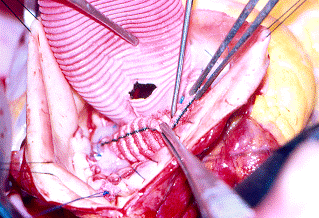

Tecnica di De Bakey e Cooley

Questa tecnica, realizzata nel 1956 da De Bakey e da Cooley, viene adoperata nei casi in cui l'aneurisma è localizzato all'aorta ascendente, con seni di Valsalva e valvola aortica normali, e prevede l'impiego di una protesi tubulare semplice di Dacron. Dopo aver cannulato l'arteria femorale o, se le condizioni lo permettono, l'aorta ascendente, una o due cannule venose vengono posizionate in atrio destro. Iniziata la CEC, la temperatura corporea del paziente viene portata a 25°C (ipotermia moderata), si clampa l'aorta ascendente prossimalmente al piede del tronco arterioso anonimo e si effettua la cardioplegia, cristalloide o ematica per via anterograda attraverso il bulbo aortico o gli osti coronarici e/o retrograda attraverso il seno coronarico. In caso di aorta calcifica "a porcellana", la CEC può essere eseguita in ipotermia profonda (18°C) ed arresto di circolo senza ricorrere necessariamente al clampaggio aortico.

La sacca aneurismatica, incisa longitudinalmente o asportata, viene sostituita da un tubo di Dacron, anastomizzato in termino-terminale sia prossimalmente che distalmente; rimosso il clamp aortico, ed effettuata una accurata purga dell'aria, si verifica la tenuta della protesi. Il paziente viene riscaldato progressivamente fino alla normotermia e, stabilizzata l'emodinamica, la CEC viene fermata.